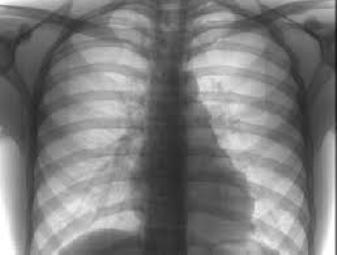

У рамках заходів до Всесвітньому Дня боротьби з туберкульозом за ініціативи громадської організації «Милосердя» та сприяння управління охорони здоров’я міської ради 25 та 28 березня 2014 року у Житомирі проводиться обстеження бездомних громадян міста з метою виявлення на ранній стадії захворюваності на туберкульоз.

Пересувний флюорограф працював 25 березня по вул. Великій Бердичівській, 113, де в взимку був встановлений пункт обігріву для безхатченків. 28 березня обстеження проводитимуть за адресою: вул. Щорса, 131. За два дні планується охопити обстеженням 80 громадян.

Голова громадської організації «Милосердя» Владислав Паламарчук розповідає: «Після зимового періоду такі обстеження є дуже важливими, оскільки дозволяють виявити хворих та вчасно розпочати їх лікування. У минулому році обстеження пройшли 49 безхатченків, у трьох виявлено відкриту форму туберкульозу та було проліковано».

Вчора флюорографічне обстеження пройшли 25 безхатченків.